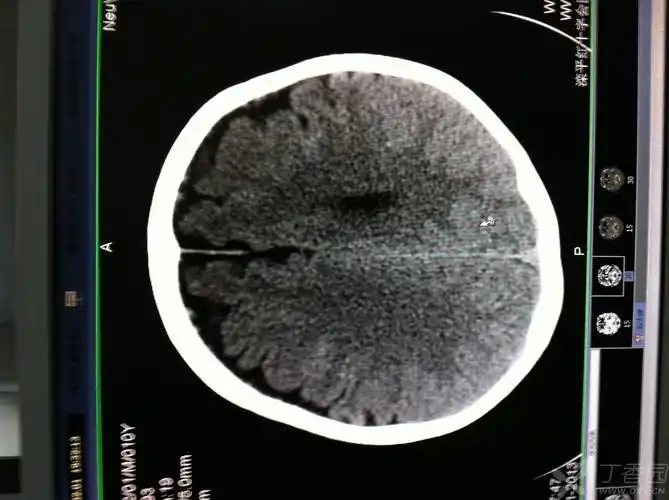

正常大脑结构是双侧对称.

1.额叶 2.半卵圆中心 3.中央沟 4.顶叶